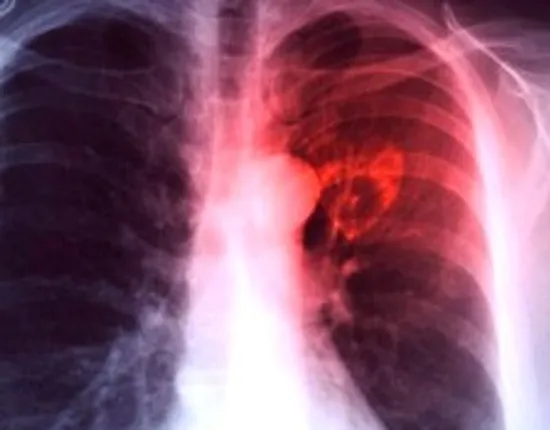

New Delhi: The Centre on Tuesday stated that about 21.69 lakh tuberculosis (TB) cases have been notified between January and October 2024. TB notification has been a concern in India, but the country has seen improvements in recent years.

“Notified TB cases increased from 18.05 lakh in 2020 to 25.52 lakh in 2023,” said Union Minister of State for health and Family Welfare, Anupriya Patel, in a written reply in the Rajya Sabha. “About 21.69 lakh TB cases have been notified between January and October in 2024,” she added.

Patel said that the National TB Elimination Programme (NTEP), under the aegis of the National Health Mission (NHM), has made significant efforts to make India TB-free. India aims to eliminate TB by 2025, five years ahead of the global target of 2030. The incidence rate of the deadly infectious disease and the related deaths have seen a major decline.

“The incidence rate of TB in India has shown a 17.7 per cent decline from 237 per 100,000 population in 2015 to 195 per 100,000 population in 2023. TB deaths have reduced by 21.4 per cent from 28 per lakh population in 2015 to 22 per lakh population in 2023,” Patel said.